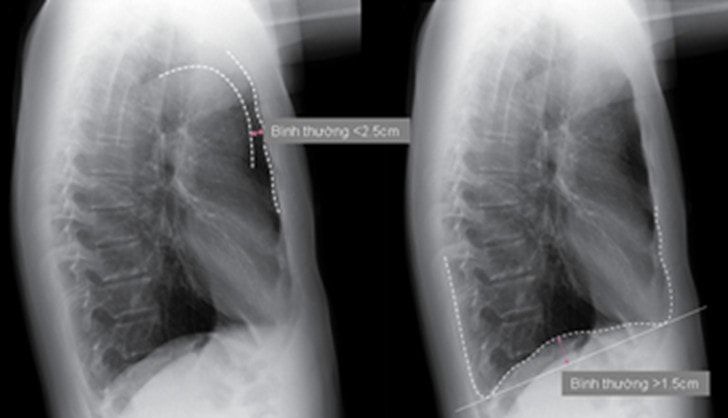

· X quang phổi: Trên phim X quang phổi thẳng có hình ảnh điển hình của khí phế thủng: Hai phế trường tăng sáng, lồng ngực hình thùng, khoang liên sườn giãn rộng, cơ hoành dẹt và hạ thấp với vòm hoành thấp hơn đầu trước xương sườn 7.

Phim phổi nghiêng có hình ảnh tăng đường kính trước sau, tăng khoảng sáng sau ức > 2.5cm (tính từ bờ sau xương ức ngang mức liên sườn IV tới quai động mạch chủ). Cơ hoành dẹt với độ cong cơ hoành < 1.5cm.

Hình 2: Hình ảnh khí phế thủng trên phim X quang ngực thẳng và nghiêng